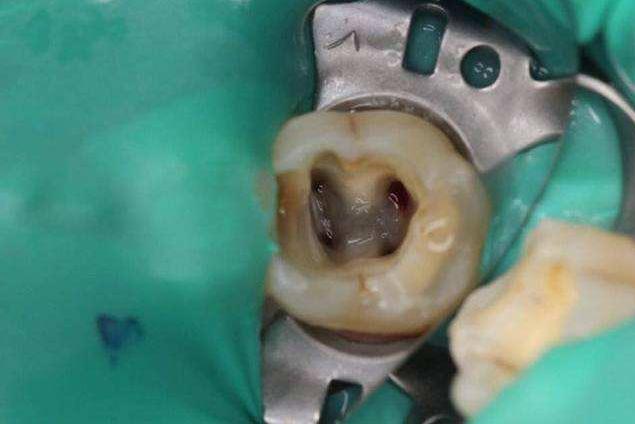

这是因为如果牙齿需要根管治疗的话,一般已经是没有完整的牙冠了的,且牙体表面并不是整齐的缺损,是有一定的尖锐棱角的。

而根管治疗后,牙体髓腔内部的物质已经被部分或者是全部清除了,这样牙体是处于一个中空状态的,所以牙齿会相对来说比较脆弱一些,那么如果患者咀嚼较硬的食物的话,就很容易对剩余的牙体造成伤害,出现劈裂或者是崩断的状况。

1,根管治疗是需要开髓的,那么牙体上部分是被清除的,在形态上牙齿就会少一部分,做牙冠会在很大限度上恢复牙齿的外观形态及使用功能。

2,根管治疗是需要在清理掉感染物质后填充药物到髓腔内部的,如果一直处于开髓后的牙体状态的话,对于后期的恢复不利,也会更容易使细菌进入到患牙深层内部。

3,开髓后的牙齿失去了牙体本来的硬组织保护,而牙髓内部的物质被清除后,牙体会变得脆弱,很容易受到外力而发生断裂。剩余牙体也容易因为失去牙髓而缺少营养补给,变得灰暗脆弱,牙冠就可以在很大程度上保护剩余的牙体不受到二次伤害。